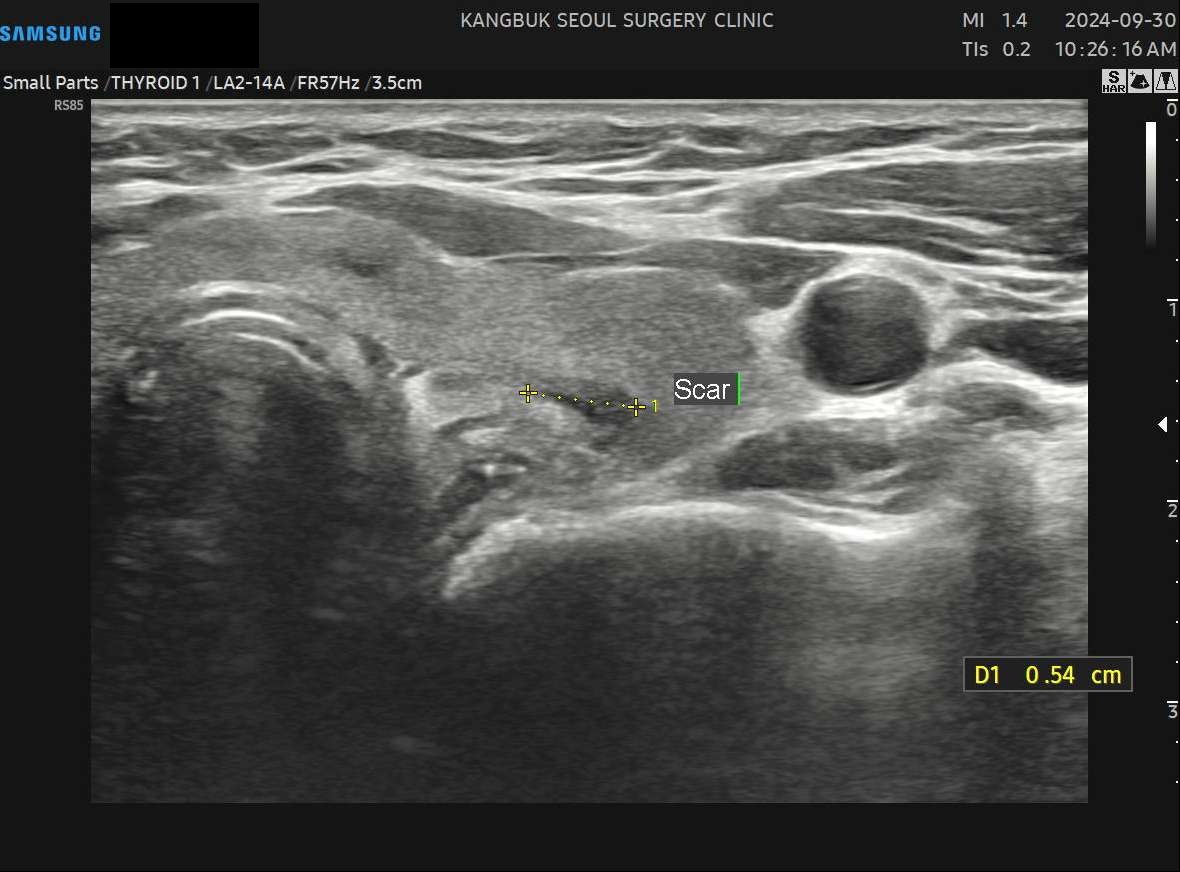

수술 14개월 후(5.4mm)사례 3